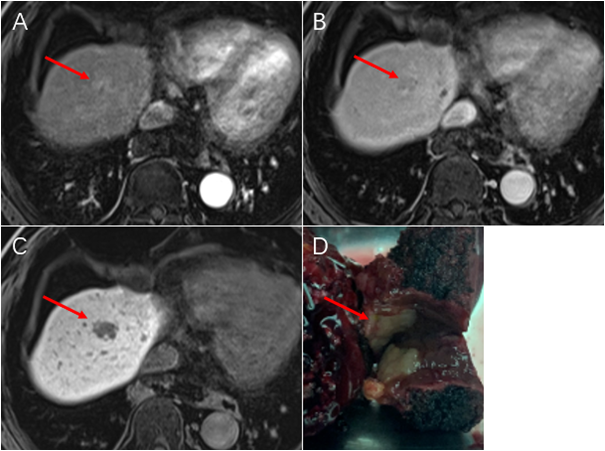

近年来,影像医学飞速发展,各种影像检查新技术层出不穷,这些新技术对临床医师诊断疾病有极大的帮助,患者也从中获益良多。 但是临床医师经常遇到这样的困惑,“这个病人/这种疾病适合哪种影像检查?”患者也常常有这样的疑问,“为什么医生要让我做这个检查?到底有没有必要?” 针对这类问题,仁济医院放射科将陆续推出一系列关于影像新技术的科普文章,期望能为广大医务工作者和患者答疑解惑,更好推动诊疗水平的提高及各类影像学新技术的运用。 李先生30岁出头,患有乙肝后肝硬化多年,今年医生让他做“肝细胞特异性对比剂磁共振增强检查”进行体检,发现肝内有一枚直径仅8毫米左右的结节,考虑为微小肝癌。 随后医生为他进行了肿瘤切除手术,病理显示为:早期的微小肝癌。由于肿瘤发现早、治疗及时,李先生术后恢复良好。 这是一种针对肝脏肿瘤的磁共振检查,检查时需要静脉内注射肝细胞特异性对比剂:钆塞酸二钠(Gd-EOB-DTPA)。 钆塞酸二钠除了具有与传统磁共振细胞外对比剂相似的功能以外,还可以通过肝细胞膜上的OATP通道转运进入肝细胞,再通过MRP通道排泄入胆道。钆塞酸二钠在肝细胞内的停留使得整个肝脏明显强化,在静脉注射后20-60分钟左右达到峰值——这段时间称为肝胆期。 2020年,全球肝癌新发病例约90万例,其中中国占了45.3%,全球肝癌死亡病例约83万例,中国占47.1%。肝癌是我国导致死亡的第2大癌症,导致如此高死亡率的最重要原因在于,我国肝癌患者超过七成为中晚期。因此,对肝癌高危人群定期进行体检,早期发现肿瘤意义重大。 肝癌高危人群通常指的是各种类型引起的慢性肝炎(特别是慢性病毒性肝炎)、肝硬化、以及既往有过肝癌病史的患者。由于肝癌大多遵循从再生结节-不典型增生结节-分化良好肝癌-分化不良肝癌的自然演变过程,监测、区分上述这些不同类型病变的性质就变得十分重要。 还记得前面提到钆塞酸二钠是通过肝细胞膜上的OATP通道转运吗?肝硬化结节从良性逐渐发展成为肝癌的过程中,伴随着正常肝细胞功能的丧失和OATP通道的逐渐减少。肝胆期病灶灰度也会表现出与周围灰白色背景明显差异的灰黑色,从而可以通过肝胆期结节在图像上灰白程度帮助判断是否已经进展到肝癌。由于肝胆期正常肝脏背景会变白,可以非常敏感的检出灰黑色的小病灶。就像在白纸上有一粒黑色的芝麻,尽管芝麻很小,但也很容易被发现。 ▲ 一例1.2cm小肝癌患者。肝细胞特异性对比剂磁共振增强检查(A)动脉期和(B)门脉期常规图像上的病灶十分隐匿。(C)20分钟肝胆期白色背景下病灶明显(红箭),灰黑色的病灶提示该结节已经进展到肝细胞癌阶段,丧失了OATP通道表达。(D)为手术的病灶剖面,病理为肝细胞癌。 ▲ 一例仅6mm的微小肝癌。肝细胞特异性对比剂磁共振增强检查(A)动脉期和(B)门脉期表现为典型“快进快出”强化方式的微小病灶(红箭)。(C)DWI弥散加权图像上轻微弥散受限。(D)20分钟肝胆期图像上结节呈灰黑色,考虑肝癌可能性非常大。右下角为手术标本剖面,病理结果为肝细胞癌。 怀疑局灶性结节增生的患者 对于非肝癌高危人群来说,肝细胞特异性对比剂磁共振增强检查主要用于判断肝内结节是否是局灶性结节增生(FNH,Focal Nodular Hyperplasia)。FNH是第二常见的肝脏良性肿瘤,由于FNH内含有正常肝细胞,因此在肝胆期上通常表现为同背景相似的灰白色,而其他类型肿瘤不含有正常肝细胞在肝胆期表现为灰黑色,从而可以进行鉴别。 有原发肿瘤病史怀疑肝脏转移瘤的人群 由于肝胆期正常肝脏强化较门静脉期更为显著,很容易发现在“白色”背景下的“黑色”小病灶。对于有原发肿瘤病史怀疑存在肝脏转移瘤的患者,肝细胞特异性对比剂磁共振增强检查可以帮助发现潜在的肿瘤微小转移灶。 检查报告结论有点复杂,啥意思呀? 对于有肝癌危险因素的患者,我们使用LI-RADS v2018版报告规范对病变进行分级。 LR-M = 高度怀疑/几乎肯定肝脏恶性肿瘤 LR-TIV = 肝脏恶性肿瘤合并静脉癌栓 LR-5 = 几乎肯定肝细胞肝癌 LR-4 = 很有可能肝细胞肝癌 LR-3 = 对于该病灶不能确定良恶性 LR-2 = 很有可能是良性病灶 LR-1 = 几乎肯定是良性病灶 LR-NC = 因技术或其他原因对病灶性质归类 对于肝脏肿瘤局部治疗后,如射频消融、经皮无水乙醇消融、冷冻消融、微波消融、动脉栓塞或化疗栓塞等的治疗反应评估,将使用以下分级(TR表示治疗反应Treatment response): LR-TR Viable = 治疗后存在活性肿瘤 LR-TR Nonviable = 治疗后无活性肿瘤 LR-TR Equivocal = 治疗后肿瘤活性不确定临床故事